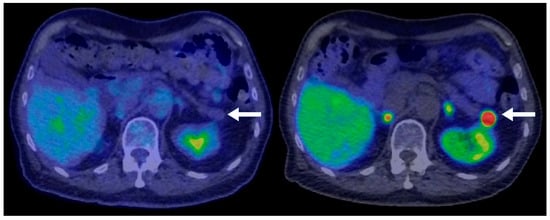

A total of 77 PNEN cases were identified over the study period, of which 39 met the inclusion criteria (Table 1). Cross-sectional imaging was available for all included cases, with CT being the initial modality in 90% and MRI in 10%. Additional imaging with 68Ga-DOTATATE PET or FDG-PET was performed in 82% of cases. Typical PNENs accounted for 54% of the cohort and were characterized by well-defined, hypervascular solid lesions (Figure 1, Figure 2 and Figure 3). In contrast, atypical PNENs comprised 46% (n = 18), including 7 cystic lesions (18%) and 11 hypoenhancing lesions (28%).

Figure 2. A 77-year-old male with an incidental pancreatic mass detected on a trauma CT scan. PET-CT demonstrates that the lesion (arrows) is non-FDG-avid (left) but intensely 68Ga-DOTATATE-avid (right), consistent with a well-differentiated neuroendocrine tumor. No evidence of metastatic disease on the PET-CT.

Most cases of hypoenhancing PNENs (n = 11) presented symptomatically (64%), and the lesions were significantly larger (median size 4.8 cm vs. 1.7 cm for typical PNENs). Calcifications were observed in 9% of hypoenhancing PNENs. As pointed out, these tumors were significantly more likely to present with advanced disease compared to other PNEN subtypes (Fisher’s exact test, p = 0.016) (Figure 6 and Figure 7).

Figure 6. A 47-year-old male presenting with biliary obstruction. CT (left): Arterial phase imaging shows a 2.5 cm hypodense mass in the pancreatic head (arrow). PET-CT (right): Performed after ERCP and biliary stent placement, demonstrating an intensely FDG-avid pancreatic head mass (arrow), consistent with a poorly differentiated primary neuroendocrine tumor. Metastatic disease involving porta hepatis and peripancreatic lymph nodes, as well as liver metastases, is also evident on the PET.